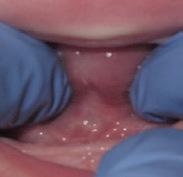

There Is Only One Smile That Matters. Yours!

You are in good hands! Dr. Makarita is the only accredited Fellow of the American Academy of Cosmetic Dentistry in Virginia.

BEFORE AFTER

At Tysons Aesthetic Dentistry Dr. Makarita has designed and equipped his practice with your smile in mind. Dedicated care and attention are just the beginning.

As a general dentist with a passion for aesthetic and cosmetic dentistry, whether a simple filling or a smile makeover, Dr. Makarita’s priority is to help you love your smile.

Since earning his doctorate from the Medical College of Virginia, Dr. Makarita has continually upgraded his skills and knowledge with continuing education so he can always bring you the most advanced options for all your dental needs.

Always welcoming new patients! Call 703-532-2020  8150 Leesburg Pike | Suite 503, Vienna VA 22182 www.ilovethatsmile.com

FREE SMILE EVALUATION In person or visit website for virtual smile consultation

Dr. H.R. Makarita

Accredited Fellow, American Academy of Cosmetic Dentistry

Master, Academy of General Dentistry

Master, International Congress of Oral Implantologists

Master, Las Vegas Institute for Advanced Dental Studies

to Love Your Smile? Dr. Makarita would love to meet you! About